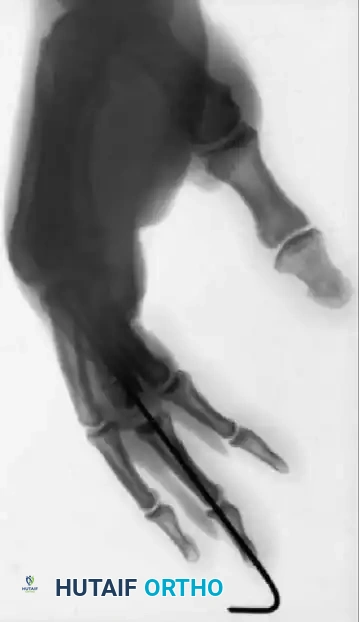

Fig. 64-5 Various techniques employed to manage middle phalangeal fractures in multidigit replantation. Combination intramedullary Kirschner wire rod and wiring in index fi nger and intraosseous wiring alone in middle fi nger with good rotational control.

Figure 64-5: Advanced Wiring Techniques.

Various techniques employed to manage middle phalangeal fractures during a complex multidigit replantation. Note the combination of an intramedullary Kirschner wire rod with supplemental wiring in the index finger, and intraosseous wiring alone in the middle finger, both achieving excellent rotational control.